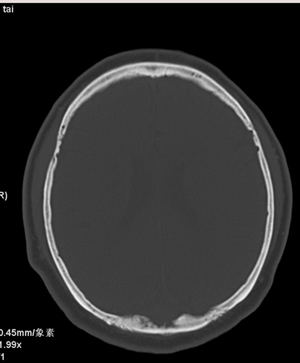

颅骨吸收破坏,病灶密度不均,周围见低密度水肿带,多考虑恶性脑膜瘤。

颅骨吸收破坏,病灶密度不均,周围见低密度水肿带,支持考虑脑膜瘤

枕骨骨质吸收破坏,局部病灶密度不均,周围见低密度水肿带,考虑脑膜瘤,建议增强扫描。